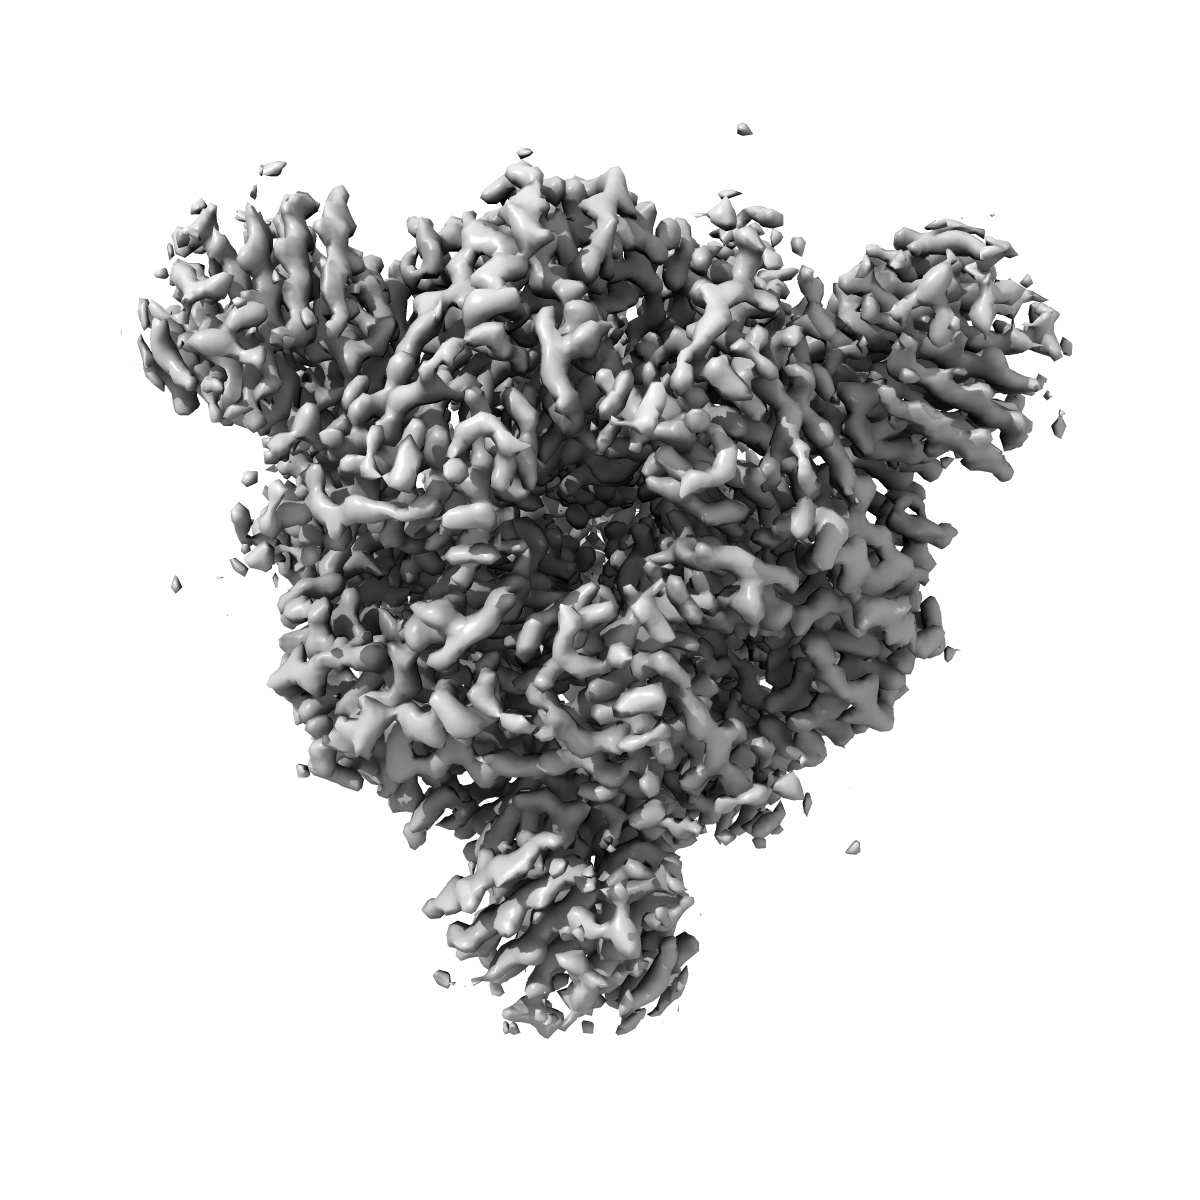

EMD-33211

SARS-CoV-2 Omicron BA.2 variant spike (state 2)

Single-particle3.25 Å

Sample: SARS-CoV-2 Omicron BA.2 spike protein